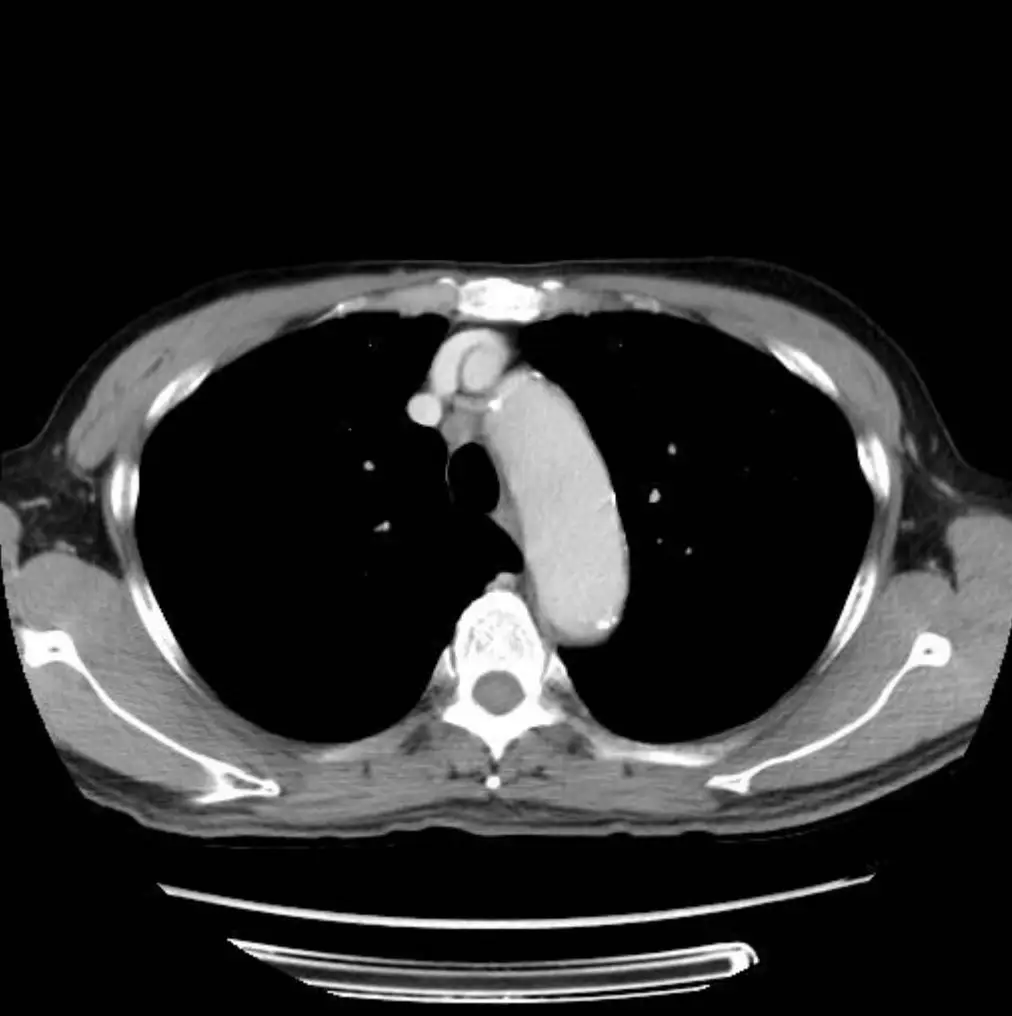

圖一(胸部電腦斷層,縱膈腔窗,心臟層面): 胸部 CT 橫切面顯示左肺(畫面右側)有一軟組織密度腫塊,位於左下葉區域,輪廓不規則,懷疑為惡性腫瘤。縱膈腔右前方(右氣管前,即 station 4R 附近)可見一枚約 1 公分的軟組織淋巴結,密度均勻,邊界清楚。主動脈弓、心臟及大血管結構清晰可辨。